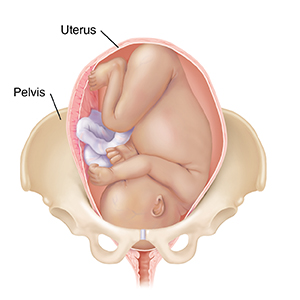

A baby (the fetus) often moves down between the pelvic bones (descend) before birth. If this is your first pregnancy, this may happen 2 to 4 weeks before labor. With repeat pregnancies, the baby may not “drop” until labor begins. The baby usually moves down headfirst. If your baby is not in a safe position for birth, or if there is a problem with the placenta, you may need special care. A cesarean section delivery may be needed.

Cephalopelvic disproportion (CPD).Baby’s head or body is too big for the pelvis.